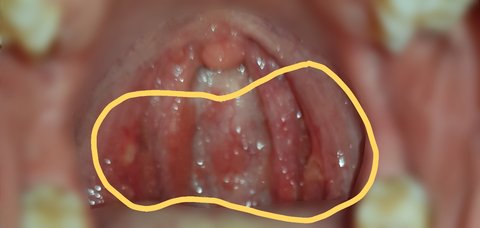

그리고 시간이 지나자 목구멍이 헐기 시작했습니다. 지금까지도 상처가 다 낫지 않은 상태입니다.

#피해자2